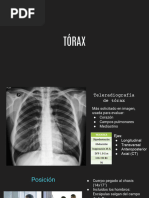

Imagenologia de torax

Métodos de imágenes:

• Radiografía de tórax

• Tomografía computarizada.

• Ecografía de tórax.

• Medicina nuclear.

• Centellograma pulmonar - gammagrafía

pulmonar.

• Tomografía emisión de positrones.

• Resonancia magnética

• Angiografía de tórax. Proyección en decúbito lateral con rayo

Radiografía de tórax: • Cuando hay un derrame que no está

Las proyecciones más comunes son PA y lateral. • En la imagen se ve el líquido en la pleura,

• Lateral izquierda que es la que está más cerca desplazado por la gravedad al estar en posición

al corazón. de decúbito lateral.

Para saber que es PA: • Normalmente las radiografías de tórax se piden

• El paciente cuando hace esta proyección está en inspiración, pero en algunos casos en

sobre un chasis y está levantando los brazos espiración.

para que el omóplato se retire del campo • Una de las cosas que se debe confirmar es

pulmonar. que esté bien inspirada.

• Las clavículas tienen disposición oblicua. • Esta se usa principalmente cuando se

Calidad de la técnica:

Proyecciones complementarias:

• Completitud

LA AP es una proyección complementaria, se usa • Penetración

en personas que no se pueden parar, niños. • Contraste

• El problema es que magnifica las cosas. • Definición - nitidez

• La disposición oblicua de las clavículas se • Centrado: rotación

pierde. • Inspiración

• Las clavículas se ven más horizontalizadas.